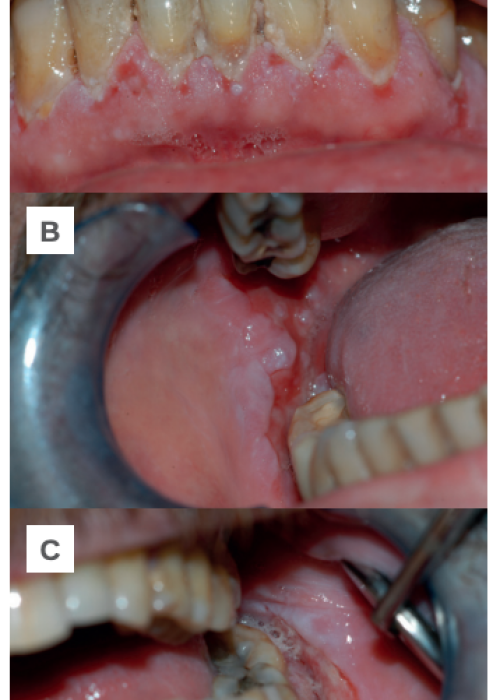

Úlcera eosinofílica lingual: a propósito de un caso clínico

Pénfigo Vulgar mucoso: a propósito de un caso. Revisión de la literatura